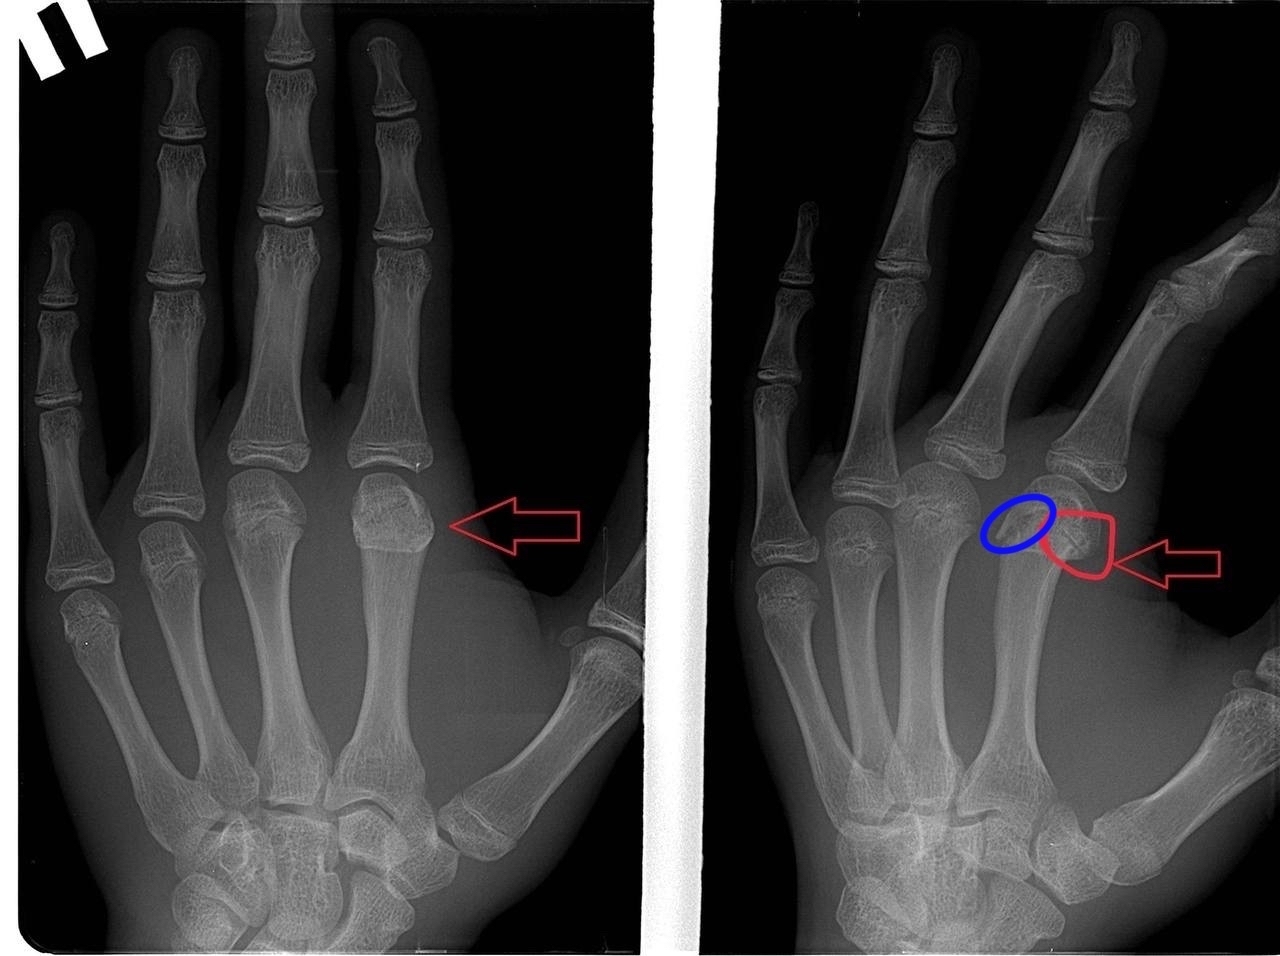

P.S. Снимки прилагаю. Разница во времени между первым и вторым - 25 дней. Был еще снимок в чисто боковой проекции, но его как-то коряво сохранили и я не отыскал его в базе.

То что вы обвели красным кружочком это зона роста:) если присмотритесь подобные линии просветления есть и на остальных пястных костях

Для вашего удобства обвёл линию перелома синим, видно дефект кортикального слоя

Второй снимок это процесс консолидации или сращения костной ткани. Линия перелома действительно прослеживается, но если обратите внимание, то заметите, что контуры уже более гладкие, сама линия менее четкая и в ней имеются более плотные участки. Это происходит формирование так называемой костной мозоли